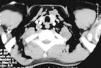

Fig. 3. Tomografía computarizada (TC) cervicotorácica del caso 1, que presentaba una lesión traqueal por arma blanca. A: cortes de TC, donde la flecha señala el nivel hidroaéreo intratraqueal. Gran enfisema mediastínico y subcutáneo. Drenaje torácico por neumotórax. B: reconstrucción de TC cervical, con flecha que señala la lesión traqueal cervical.